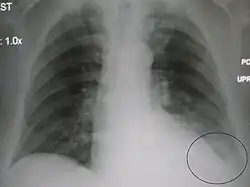

AP CXR showing pneumonia of the lingula of the left lung -

Right upper lobe pneumonia as marked by the circle. -

Left upper lobe pneumonia with a small pleural effusion.